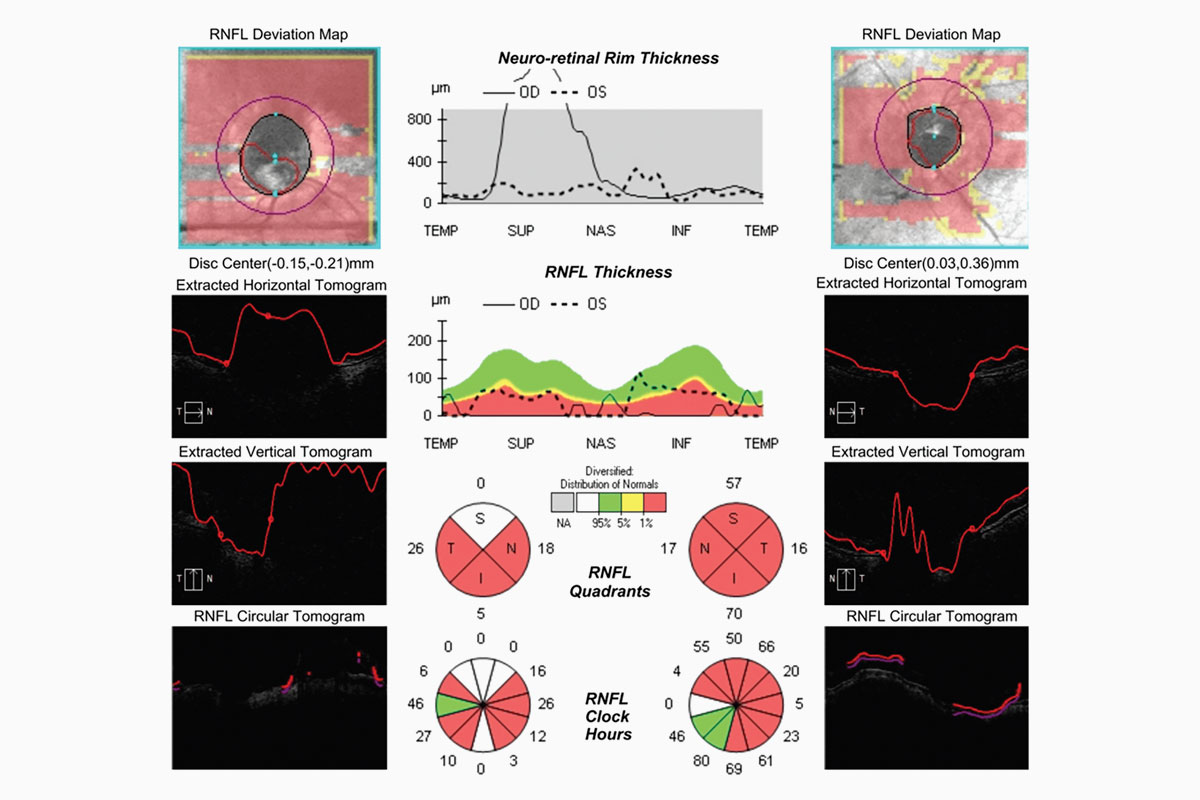

Los investigadores de Mayo Clinic identificaron dos fenotipos diferentes en pacientes con glaucoma de tensión normal. El fenotipo 1 incluyó a pacientes con factores de riesgo para el síndrome metabólico, como hipertensión, diabetes mellitus y enfermedad de las arterias coronarias, mientras que el fenotipo 2 incluyó a pacientes con síndrome de Raynaud, migrañas, anemia o hipotensión sistémica. (Cortesía de Victoria M. Addis, MD)

En el estudio, los pacientes del fenotipo 2 tenían más probabilidades de ser del sexo femenino, más joven, tener un índice de masa corporal más bajo y una presión intraocular más baja. La asociación de pacientes del fenotipo 2 con autorregulación alterada y mayor riesgo de glaucoma de tensión normal se ha descrito anteriormente.